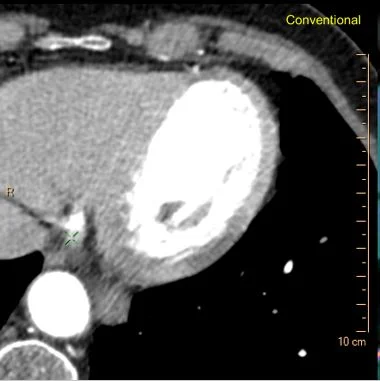

Conventional CT: Do you see the MI?